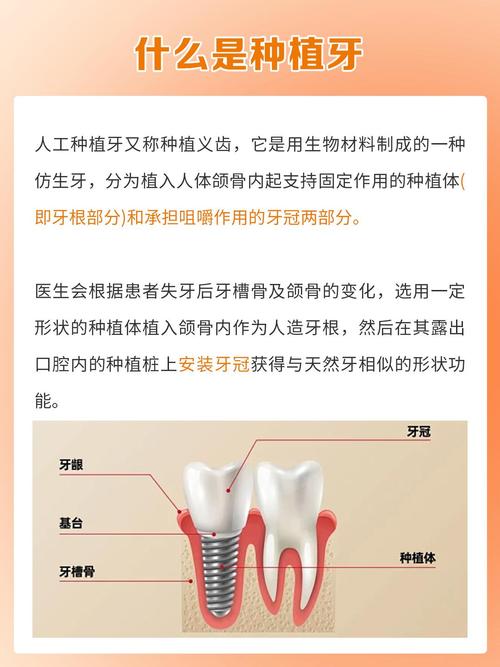

先搞懂:为什么牙槽骨对种植牙这么重要?

种植牙的核心原理是通过外科手术将纯钛种植体植入牙槽骨,待其与骨组织结合(骨结合)后,再在上方安装牙冠,这个过程就像“树扎根土壤”,牙槽骨的“质量”直接决定种植牙的稳定性、使用寿命和成功率。

正常情况下,天然牙的牙根会持续刺激牙槽骨,维持其骨量,但一旦牙齿缺失,牙槽骨会因失去“功能性刺激”而逐渐萎缩——就像长期不运动的肌肉会萎缩一样,缺牙时间越长、年龄越大,牙槽骨流失可能越严重,表现为骨宽度不足(<8mm)、骨高度不足(<10mm)或骨密度疏松,这确实是种植牙的一大挑战,但绝非“死结”。